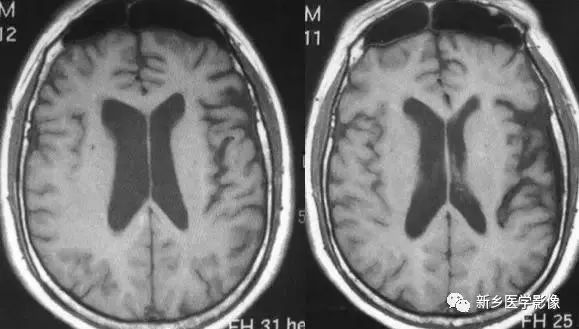

❶ 正常变异

正常人中,有相当一部分人双侧侧脑室大小不一致、不对称,一侧侧脑室明显大一于另一侧。临床上,智力及精神发育正常,无临床意义。